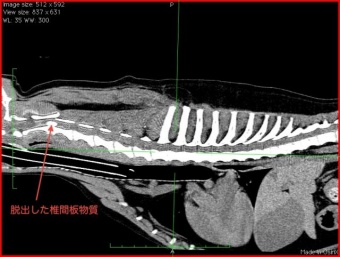

縦に切ったCT画像で見ると(左側が頭側で、背骨を薪を割るようなイメージで切った画像です。こういう風に、見たい方向で見れるのがCTのいいところですね)、右の矢印の部分だけ、下から白い椎間板物質で圧迫されているのがよくわかると思います。